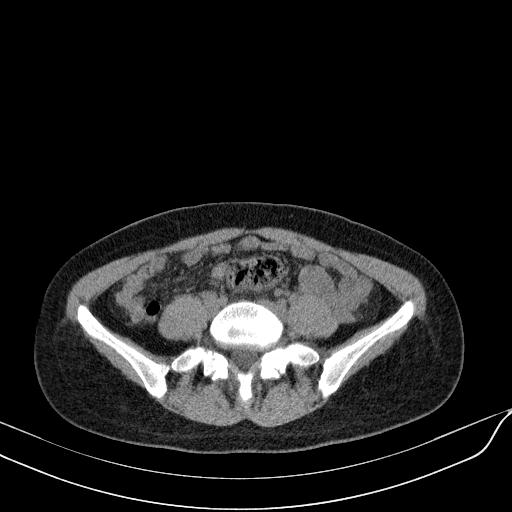

标题: CT23965:无外伤史,下腹痛 [打印本页]

标题: CT23965:无外伤史,下腹痛

肠道未准备,继续往下扫,乙状结肠占位不排除。建议钡灌或结肠镜检查。

乙状结肠占位不排除

未见明显异常改变,做个气钡双重造影除外一下结肠病变,无外伤史为啥不常规喝泛影葡胺水对比剂再扫ct呢?

回肠间质瘤?

肠道肿瘤,建议行钡剂灌肠检查。